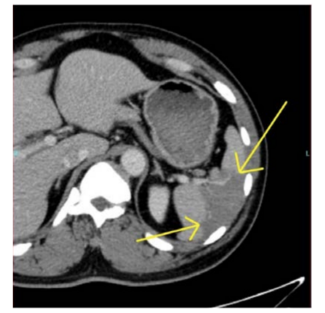

James L. Thomas, MD; Delton Farquharson, MBBS

The authors present a case of spontaneous dissection of the splenic and hepatic arteries, which was treated nonoperatively.